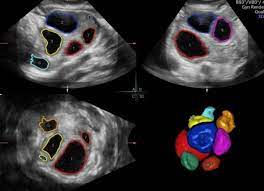

The basis of the effectiveness of the ultrasound system is intelligent solutions and medical imaging tools. First of all, ZST + and STE are the key to creating accurate and detailed images, their research, and analysis. The intelligent ZST+ platform allows you to transform ultrasound and create images in high spatial and temporal resolution.

- Sound sensory elastography STE. Shear wave elastography, implemented in Consona N8, provides: improving the quality of the assessment of the stiffness of the study area; increased sensitivity and deep penetrating power; reliable quantification with high repeatability. The result is a two-dimensional color elastogram and an accurate assessment, indispensable in the diagnosis of the abdominal cavity and small pelvis.

- High-precision hemodynamics HR Flow. Mindray technology displays blood flow with greater spatial and temporal resolution even in the case of small vessels.

- Clear display of small and overlapping vessels. Glazing Flow is a color/power Doppler flow technique with 3D visualization that complements the study of hemodynamics and the structure of small and overlapping vessels.

- Real-time 4D visualization with iLive. Mindray Consona N8 realizes high-speed volumetric visualization of superficial and internal anatomical structures, which guarantees: photorealistic representation of details; 4D rendering with multiple lights.